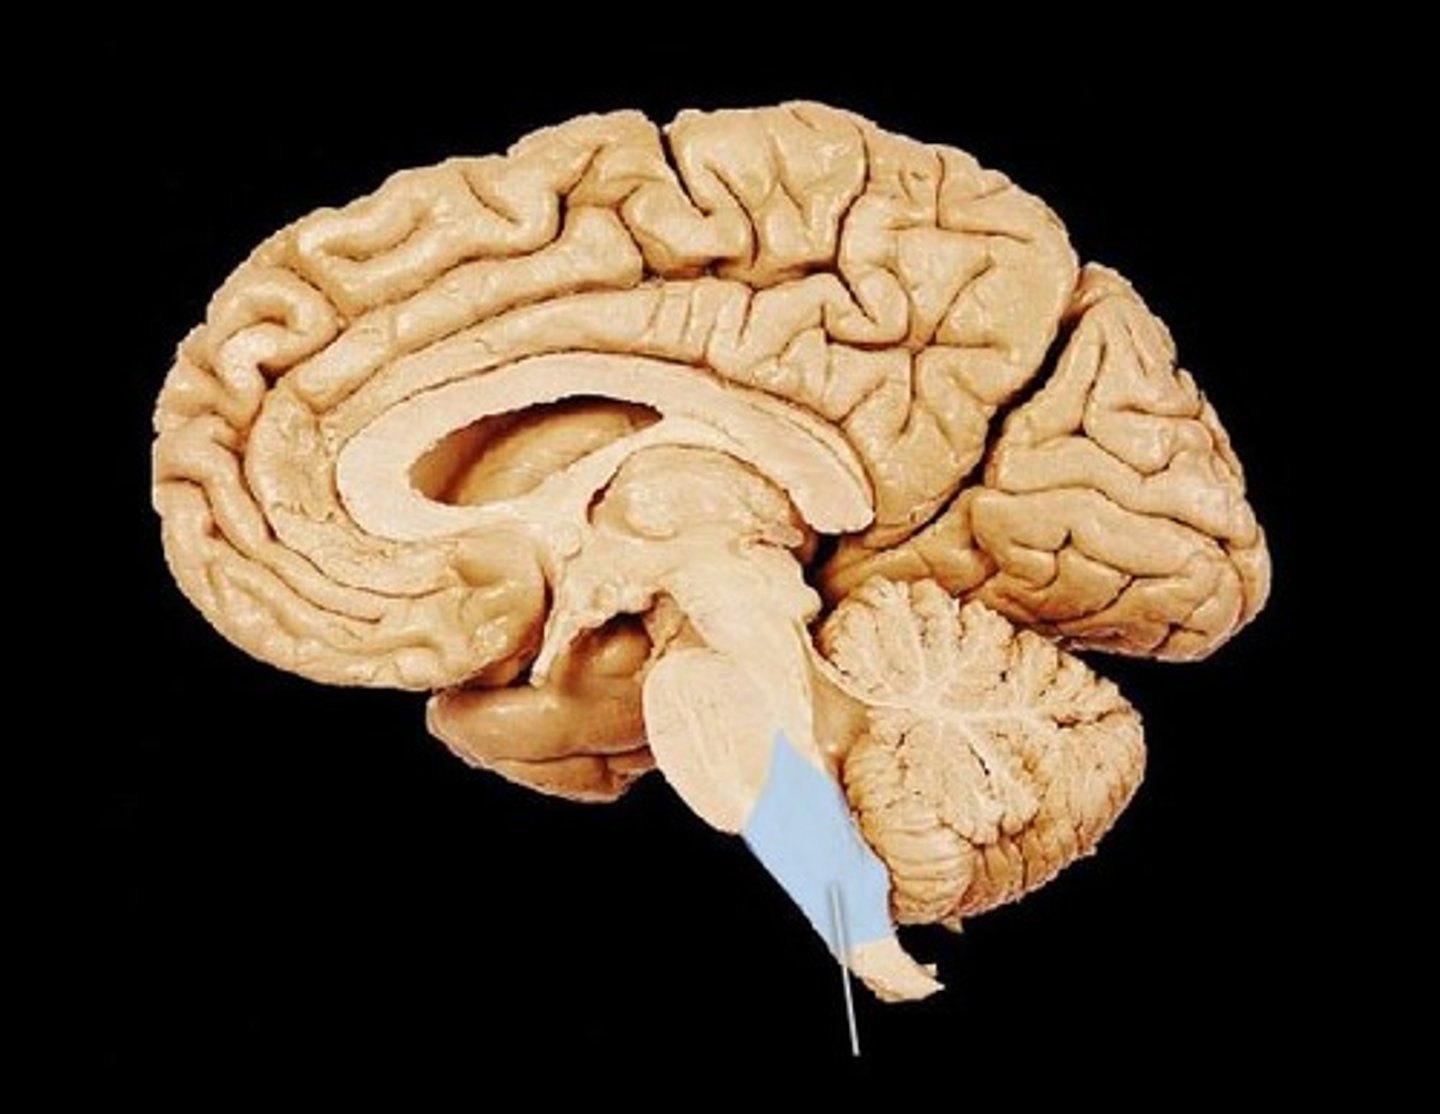

MIdsagittal View of brain

Lateral Ventricle

Third Ventricle

Cerebral Aqueduct

Forth Ventricle

Corpus Callosum

Fornix

Thalamus

Pineal Gland

Superior Colliculi

Inferior Colliculi

Midbrain

Hypothalamus

Cerebral Cortex Gray Matter (nerve cell bodies)

White Matter (myelinated nerve fibers)